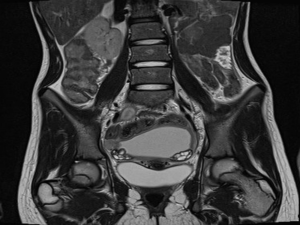

МРТ органов малого таза проводят в несколько последовательных этапов. Первым из них является обзорный снимок таза, с помощью которого выясняют общие моменты: наличие или отсутствие органов, их общее состояние, локализацию и взаимное расположение в малом тазу. Далее получают срезы в разных режимах, импульсных последовательностях и проекциях.

МРТ — наиболее информативный метод исследования органов малого таза, используемый в диагностике заболеваний мочевого пузыря, прямой кишки и репродуктивных органов. Обеспечивает многоплоскостную и трехмерную визуализацию анатомии в норме и при патологии, это.

Часто, классического физического обследования недостаточно для оценки причин дисфункции органов тазового дна. МР-сканирование позволяет получить снимки с контрастом как костных, так и мягких тканей и дает возможность оценить степень развития, размеры и точную локализацию инфекционных, воспалительных и опухолевых процессов.

Магнитно-резонансная томография органов малого таза позволяет изучить анатомию мочевого пузыря и мочевыводящих протоков, нижних отделов кишечника, мускулатуры, органов репродуктивной системы, а также выявить причину женского или мужского бесплодия. Информация, полученная во время сканирования, используется врачами при постановке диагноза, планировании стратегии медикаментозного или хирургического лечения.